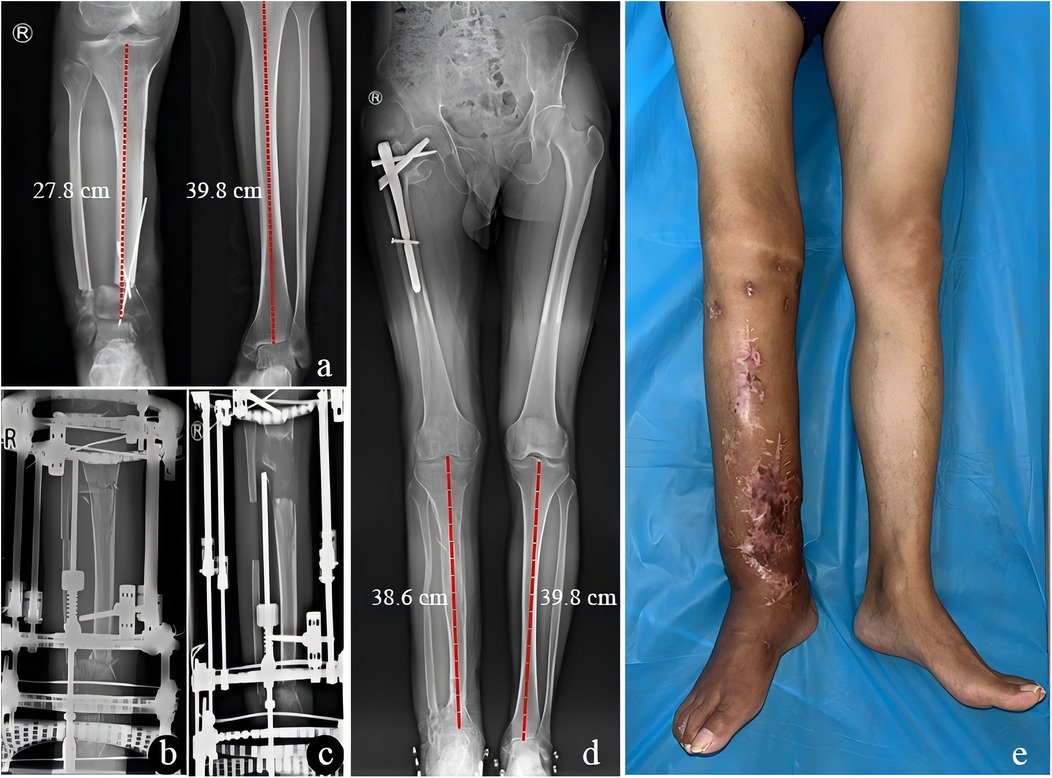

Figure 3

X-ray images and a photo of legs. The X-rays show orthopedic measurements with marked lines and instruments. The left X-ray indicates 27.8 cm and 39.8 cm measurements. The middle X-ray shows a hip with surgical pins. The right X-ray also displays a measurement of 38.6 cm and 39.8 cm. The photo shows a leg with visible scars and surgical marks standing on a blue surface.

Figure 3. A 37-year-old male with limb shortening deformity after replantation of lower leg amputation treated by limb lengthening. (a) Successful limb salvage and replantation of the affected limb after shortening approximately 12 cm. (b) x-ray of the right tibia before limb lengthening. (c) Three months after limb lengthening. (d,e) The implantation of the Proximal Femur Bionic Nail (PFBN) in the proximal femur for initial intertrochanteric fracture may not affect the overall study findings, as it had no impact on the primary endpoint of limb length discrepancy correction or the functional outcomes based on tibial measurements. The consolidation phase was completed with satisfactory bone and functional outcomes after 19 postoperative months.